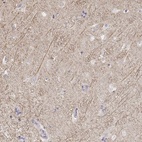

Immunohistochemical staining of human hippocampus shows moderate cytoplasmic positivity in neuronal processes.